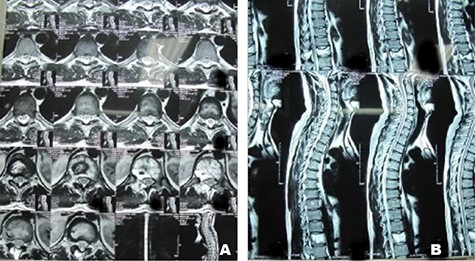

A 26-year-old male presented with pain over the lower lumbar area. Physical examination and laboratory tests were unremarkable with no neurologic deficit. X-ray and CT scans showed a lytic lesion with a sclerotic border in the right half of the body of the L5 vertebra (Figs 6 and 7). MRI showed a well-defined low signal lesion in T1 weighted images and high signal lesion in T2 weighted images (Fig. 8). The bone scan was negative. The patient underwent surgery and the lesion was extracted through the right pedicle and the remaining cavity was filled with an autologous bone graft from the iliac crest and right-side posterior fusion was done from L4 to L5 (Fig. 9). The pathology report was consistent with SBC. The patient had no recurrence seven years after surgery.

Case 2, Sagittal T2-weighted and T1-weighted MR images of lumbar vertebrae show the body and homogeneous cystic lesion of L5.